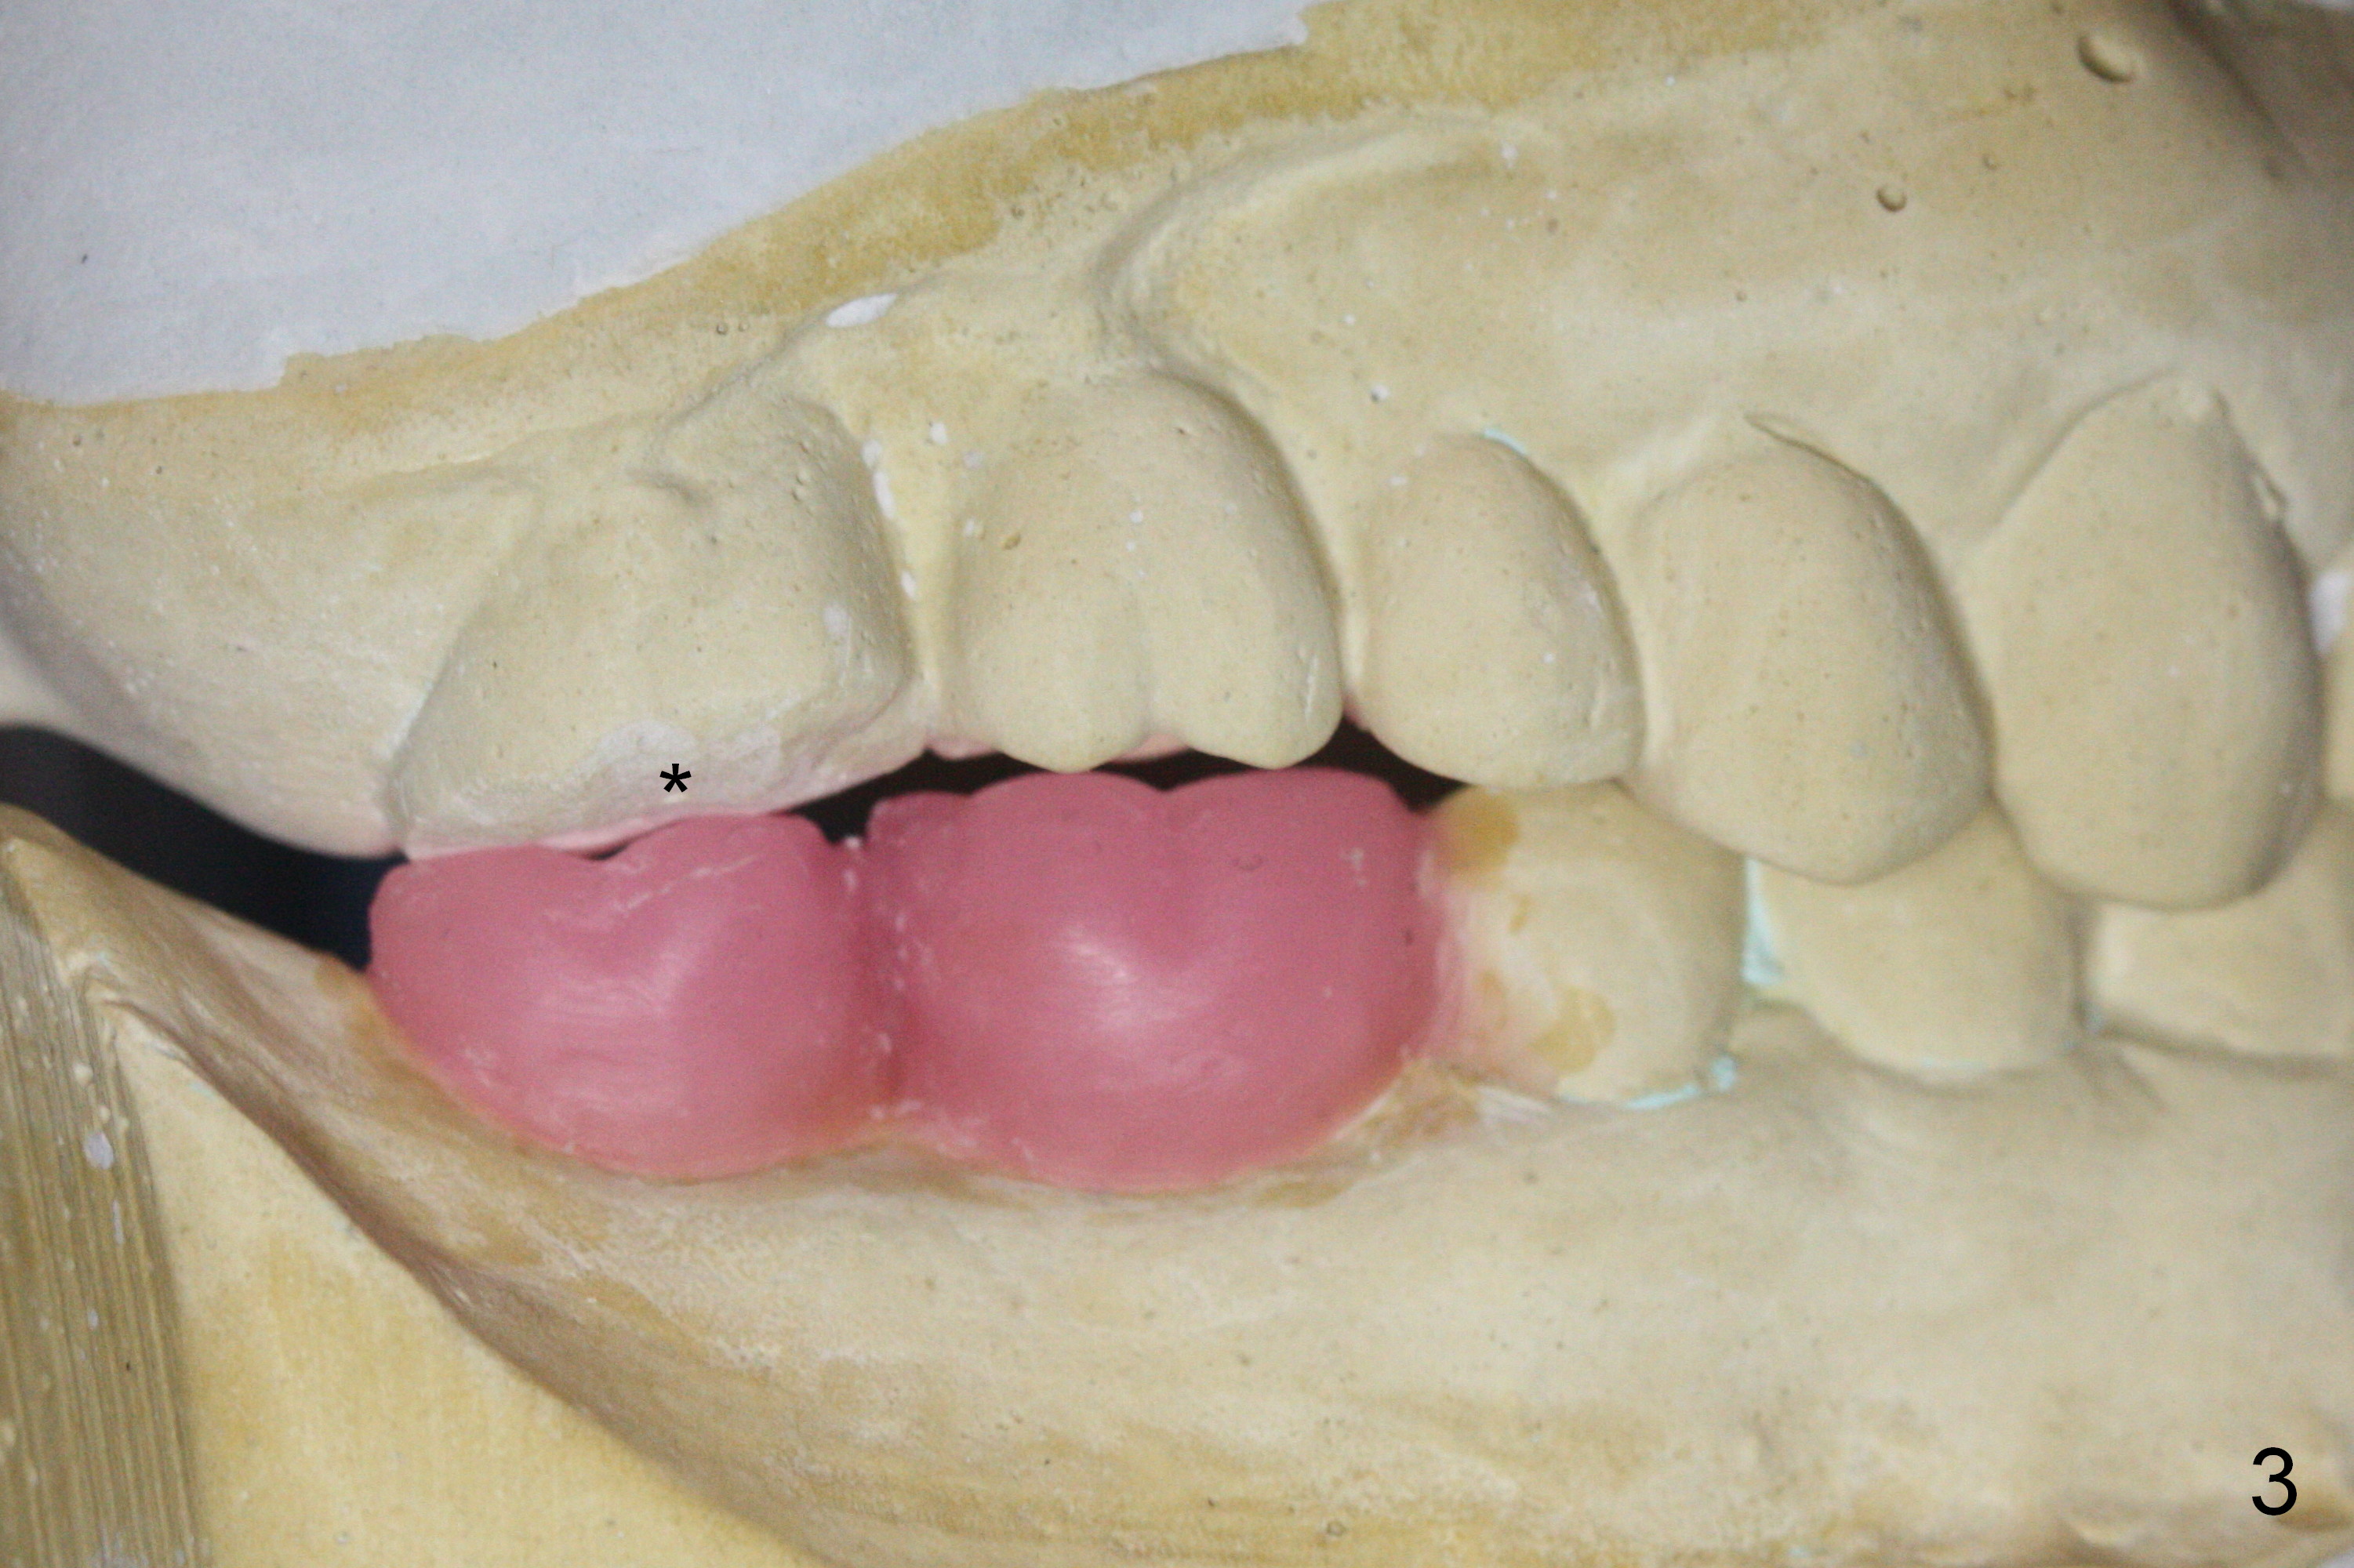

A surgical stent for the lower right quadrant is to be placed as a guide to reduce #2 occlusion (Fig.3 *).  Wax up shows that the pontics at #3 and 4 are infraocclusal.  It appears that the upper right bridge should be removed.  Implants are placed at #3 and 4 and new crowns are fabricated at #2 and 5 to have normal occlusion.